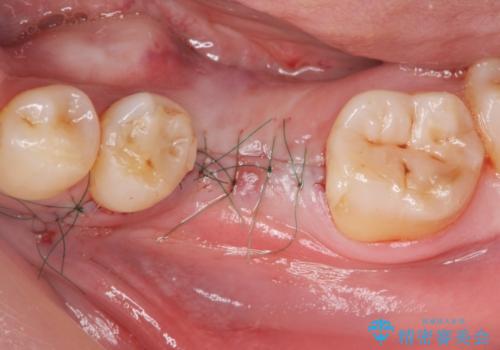

- 歯を破折により失い、インプラント治療を希望され来院されました。

インプラントを埋入し咬合機能を回復するとともに周囲の骨造成も同時に行っていきます。

インプラントを適切な位置に埋入することで、清掃性が高くしっかりと咬合力に耐えられるようなインプラント治療を行うことができます。